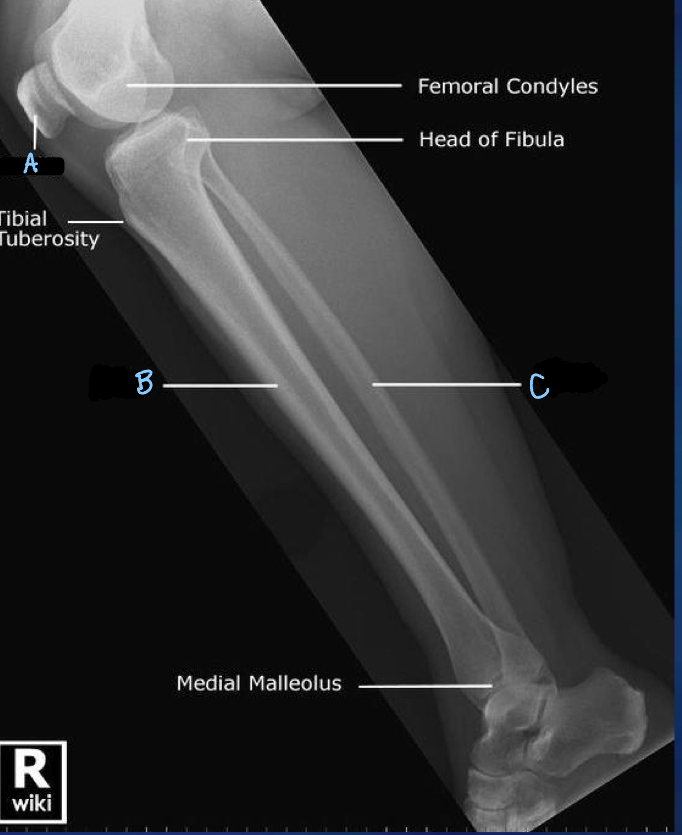

1

lateral tibial condyle

What is B?

fibula

What is C?

medial tibial condyle

What is D?

tibia

What is A?

patella

6